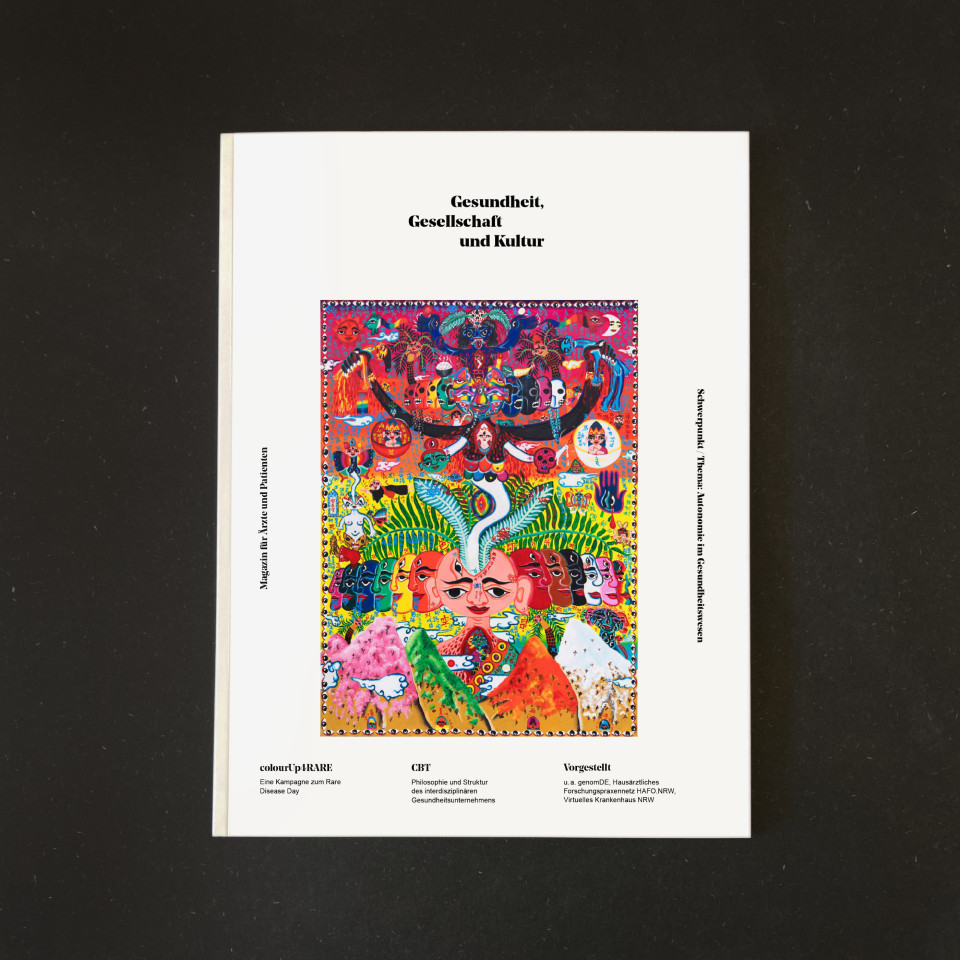

Redesign of CBT Magazine

Magazine